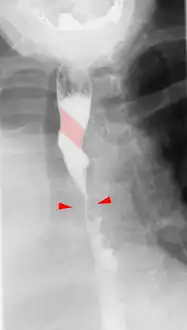

This condition is usually asymptomatic.[1] The aberrant artery usually arises just distal to the left subclavian artery and crosses in the posterior part of the mediastinum on its way to the right upper extremity.[2] In 80% of individuals it crosses behind the esophagus.[2] Such course of this aberrant vessel may cause a vascular ring around the trachea and esophagus. Dysphagia due to an aberrant right subclavian artery is termed dysphagia lusoria, although this is a rare complication.[2][3] In addition to dysphagia, aberrant right subclavian artery may cause stridor, dyspnoea, chest pain, or fever.[1] An aberrant right subclavian artery may compress the recurrent laryngeal nerve causing a palsy of that nerve, which is termed Ortner's syndrome.[4]

The aberrant right subclavian artery frequently arises from a dilated segment of the proximal descending aorta, the so-called Diverticulum of Kommerell (which was named for the German radiologist Burkhard Friedrich Kommerell (1901–1990), who discovered it in 1936).[5][6] It is alternatively known as a lusorian artery.[1][3]